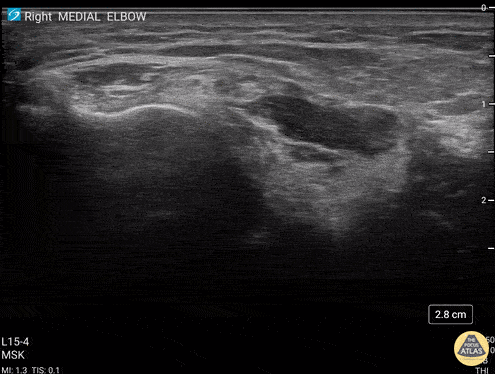

59 y/o M presented with 1 year history of insidious onset R medial elbow pain especially worse with playing golf and was found to have a high grade tear of the common flexor tendon. Video shows coronal view scanning posterior to anterior at the medial epicondyle (right is proximal). There is decreased echogenicity throughout the entire length of the tendon, but normal fibrillar tendon appreciated at deep aspect of tendon. There is an enthesophyte noted at the insertion site. Eben Alexander, DO Devesh Patel, MD Eastern Virginia Medical School